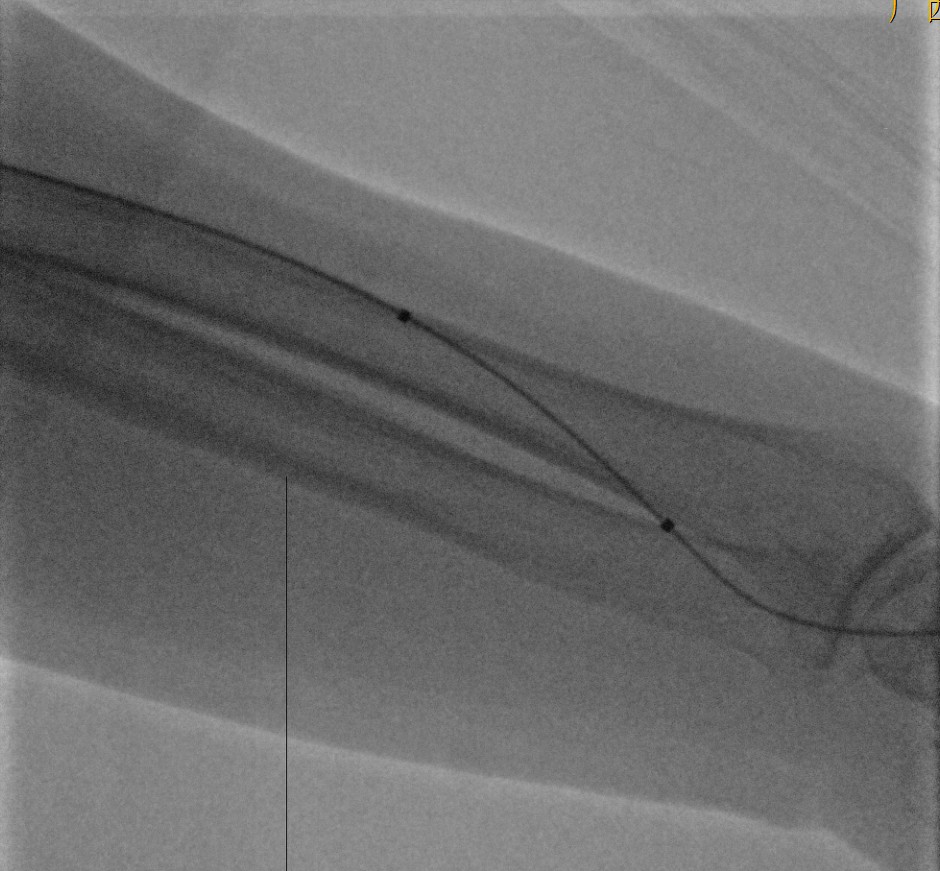

术中造影的结果和术前判断的一样:吻合口上方多发狭窄,合并血栓闭塞。

造影见吻合口区头静脉两个狭窄

图片说明:应用4F单弯造影发现实质性狭窄